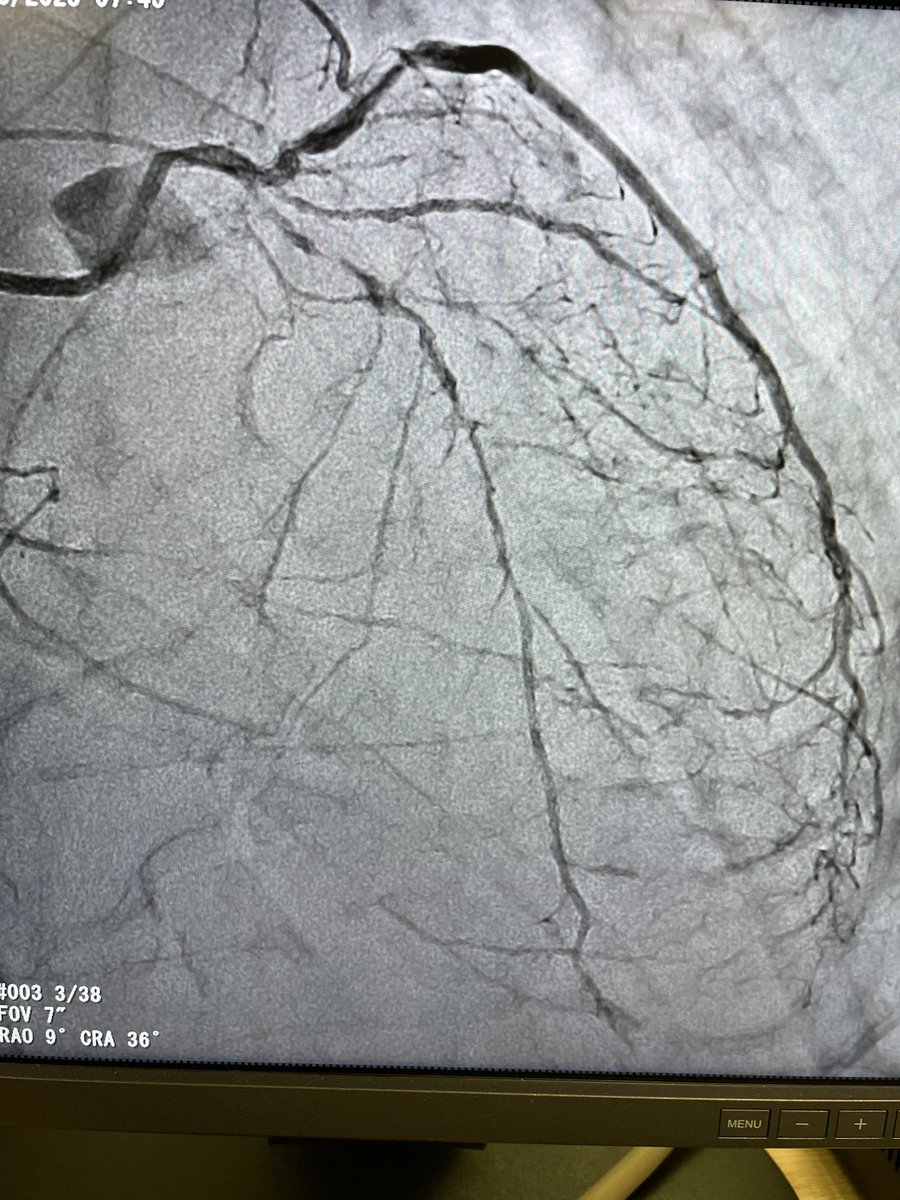

@KovacicMihajlo Agree with everyone on initial management. If decided on stent route, prepare everything for distal embolization management. Suggest no aggressive post dilation fo stent if adequate stent expansion on IVUS.